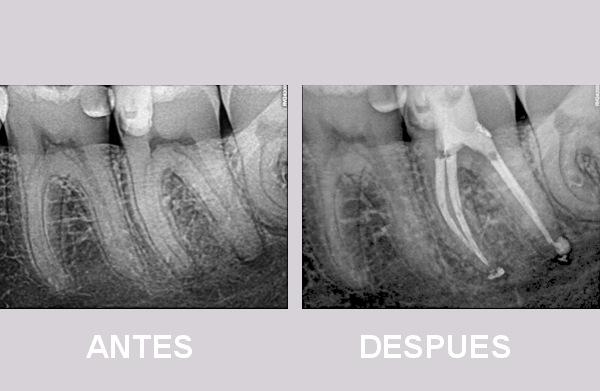

ENDODONCIA

Es un tratamiento dental que consiste en limpiar y sellar el interior de un diente dañado o infectado (la pulpa), eliminando el tejido enfermo para salvar la pieza dental y evitar su extracción.

- Limpieza: Se extrae la pulpa infectada o dañada, se limpian y desinfectan los conductos radiculares.

- Obturación: Los conductos vacíos se rellenan con un material biocompatible y se sella la apertura.

Contamos con anestesia electrónica y radiovisiógrafo que nos va a dar una imagen digital de alta precisión, con la mínima radiación al paciente.